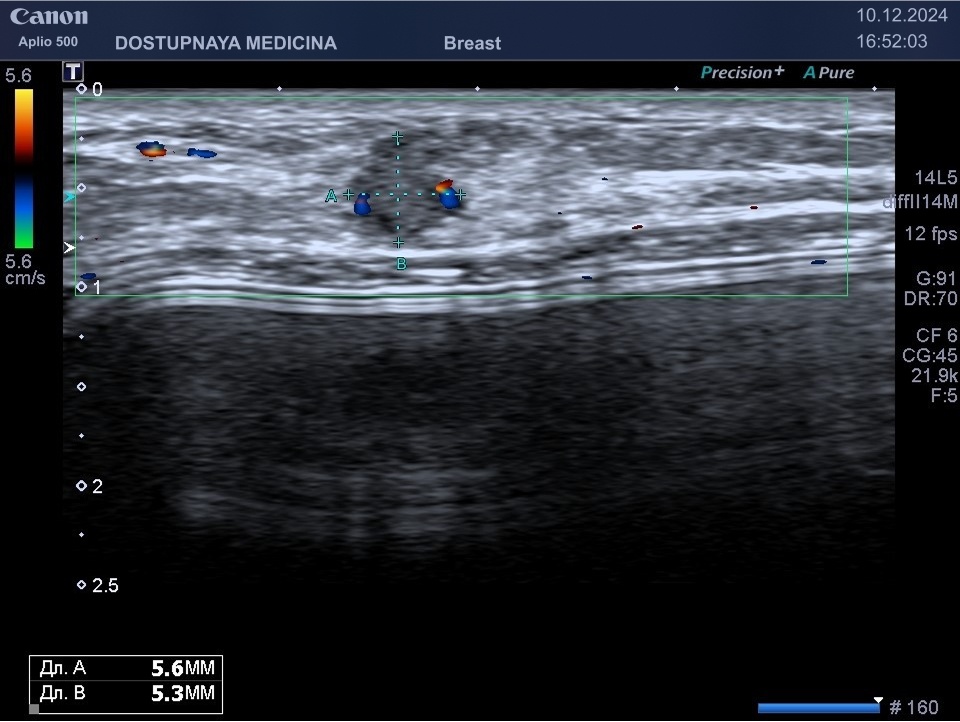

Кисты могут воспаляться, тогда при ультразвуковом исследовании в режиме ЦДК вокруг кисты отмечается усиление кровотока, пациентка при этом жалуется обычно на уплотнение и боль в области кисты молочной железы. Воспаление кисты может привести к её абсцедированию.

При ультразвуковом исследовании в кисте может быть визуализирован папиллярный компонент с кровотоком в режиме ЦДК. Так могут выглядеть цистаденопапилломы, которые считаются аблигатным предраком.